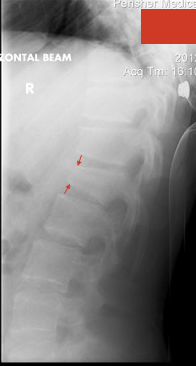

Lesson 4 / Beware the patient who has landed hard on their back and been winded. They probably have a wedge compression fracture even if they have no posterior midline tenderness.

Personally, I’m a bit of a coward approaching fifty, so only go into the terrain parks designed for ten year-olds. It works for me and I don’t get injured. However, not everyone is like me and we see a lot of people (usually males) who have landed hard on their backs or flat onto their skis or boards. The former can have thoracic spine fractures: those that scorpion get their fractures at the thoracolumbar junction and those that land hard on their feet can get lumbar spine fractures or even fractures at multiple levels.

We are taught to roll the patient and examine them for spinal tenderness, and of course that is worth doing. But, some anterior wedge compression fractures present without posterior mid-line tenderness, particularly those in the thoracic spine. Patients have generally been winded and their pain may be retrosternal rather than in their back (remember how visceral pain is quite non-specific).